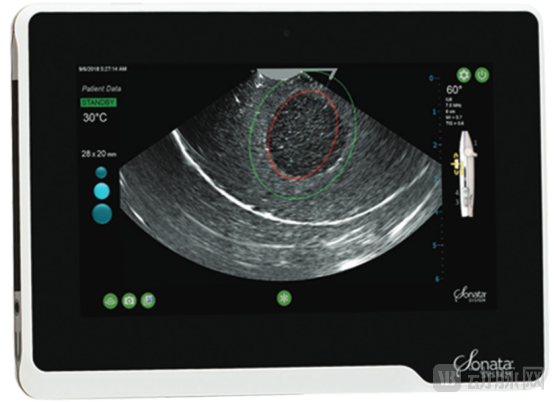

Sonata图像引导软件(GGS)具备智能定位、消融及规划功能,能在超声图像上叠加显示消融区和热安全边界,帮助医生精确选择消融目标和部署位置,避免正常组织受损。手术过程中,医生将Sonata治疗设备通过阴道和子宫颈送入宫腔,利用子宫内超声探头精准定位肌瘤,并通过手柄上的紫色操纵杆调整消融区域的大小和深度。消融时间根据肌瘤大小而定,通常为1至7分钟。

视屏中红色椭圆表示制定的消融区域,绿色的椭圆表示热安全边界,热安全边界在整个手术过程中必须始终位于子宫浆膜层内